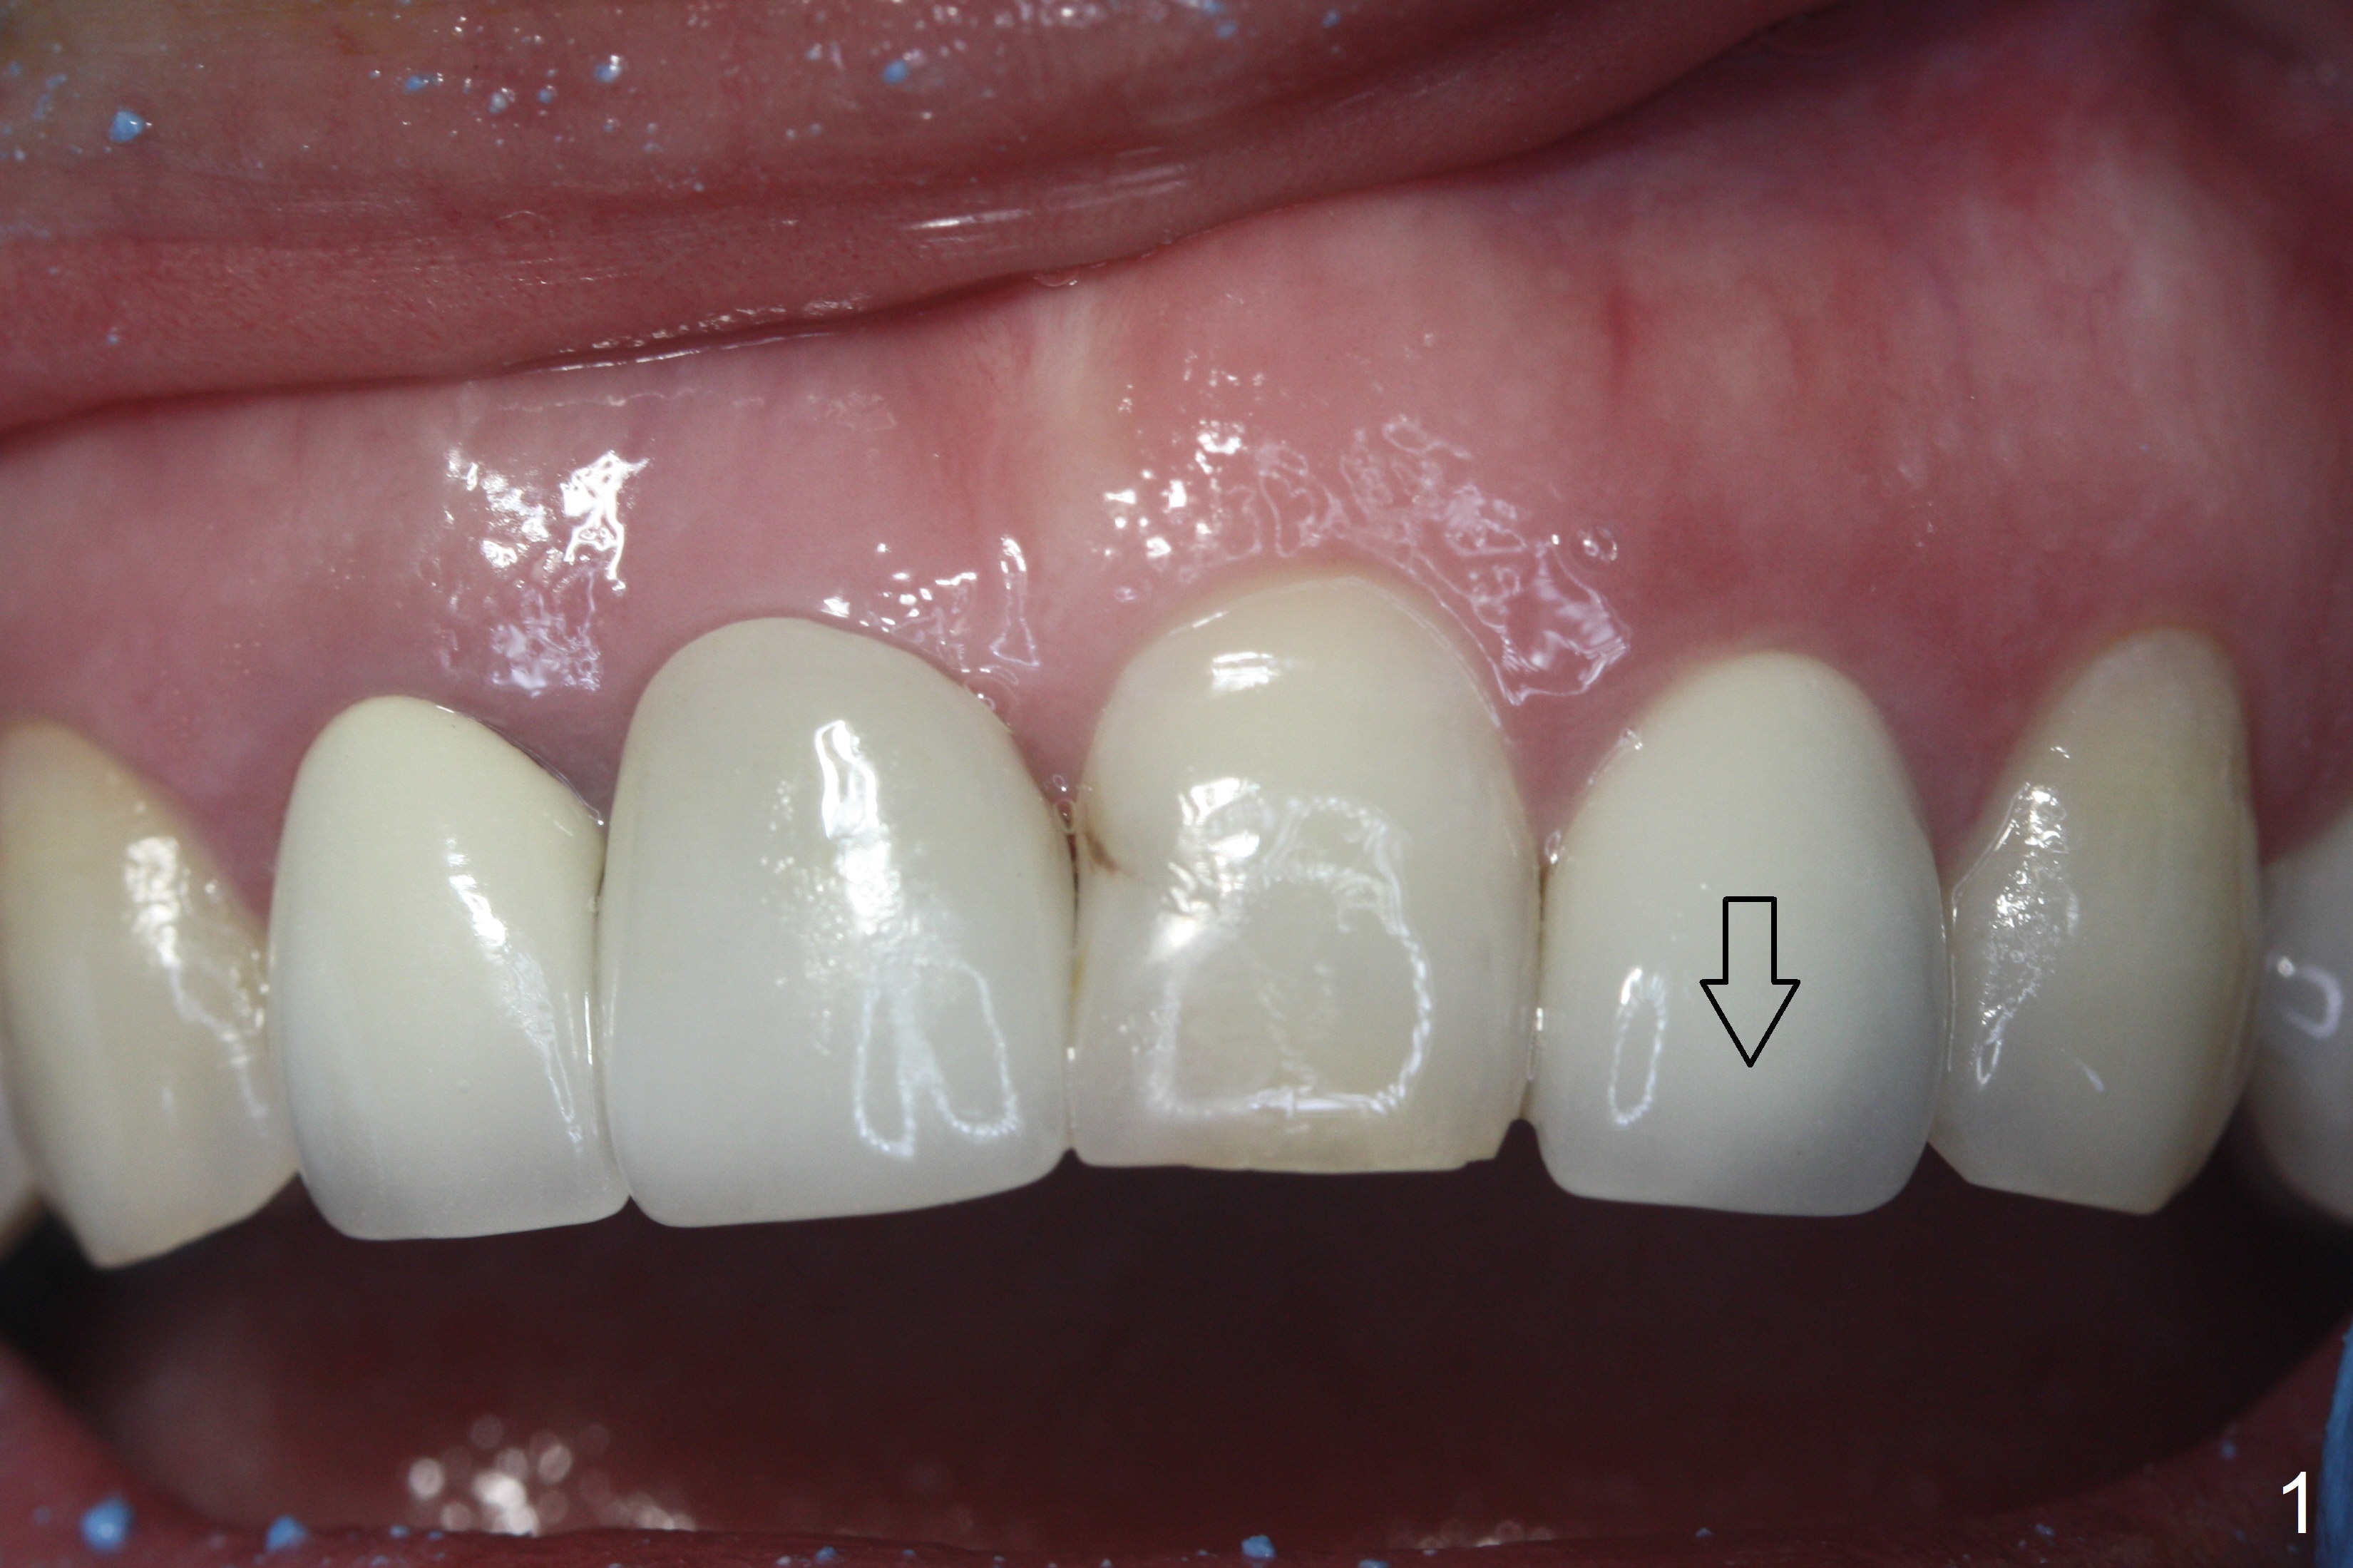

When the patient returns, the crown at #10 has displaced incisally (Fig.1,2 arrow). The initial depth is 15 mm (Fig.3, palatal gingival margin). After a 3.8x12 mm SM implant is placed (Fig.4), allograft is packed in the peri-implant space (*, as compared to Fig.3) and a 3.9x4(3) mm abutment is placed (A). More allograft is placed in the peri-abutment space (Fig.6 *). The existing crown (Fig.4,5 C) is hollowed, relined (R) and used as an immediate provisional (Fig.7-9). The patient is pleased with the appearance of the apically-repositioned provisional (Fig.7 arrow). She returns for impression 3.5 months postop (Fig.10). After change of abutment to 3.9x4(4.5) mm and new provisional, impression is retaken 5 months postop (Fig.11,12). It appears that the implant is palatally placed and a little large for the site (Fig.11 (B: buccal); Fig.12 (^: thin layer of the palatal plate)). If an angled abutment were used, a screw-retained crown might have been feasible. Due to the new provisional, the gingiva looks healthy when a permanent crown is cemented (Fig.13).